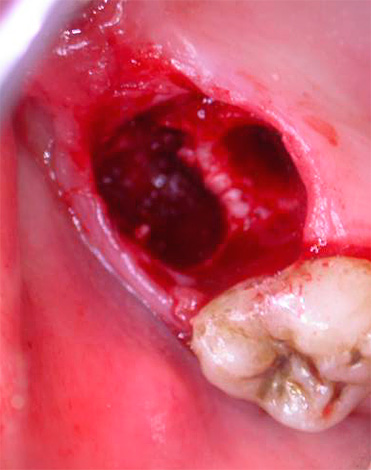

Sangramento grave de um buraco em um dente do siso removido

Sangramento após remover um dente do siso na mandíbula inferior ocorre com mais frequência do que quando os dentes 5, 6 ou 7 inferiores são removidos, porque ao redor do G8 há suprimento sanguíneo abundante para o tecido gengival, e a complexidade do próprio procedimento de remoção desempenha um papel importante aqui, quando os tecidos circundantes são gravemente feridos. O sangue pode não parar por muito tempo: nesses casos, o cotonete de gaze deixado pelo dentista-cirurgião no orifício está saturado com sangue.

Esse sangramento pode durar de várias horas a um dia.